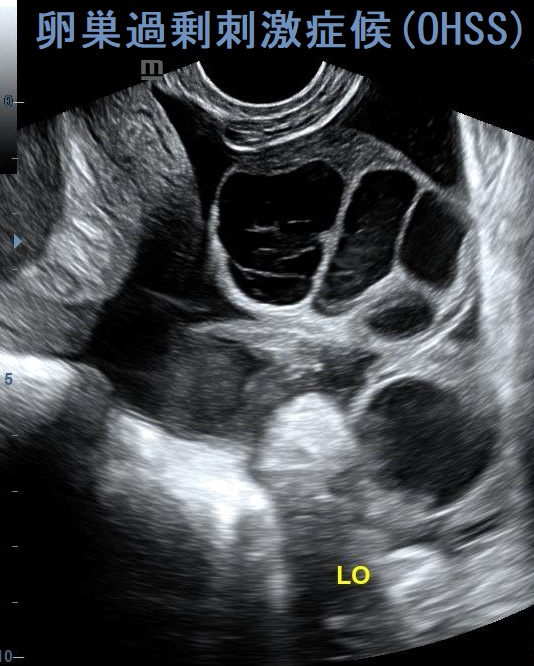

卵巣過剰刺激症候群(OHSS) 経腟超音波(エコー)画像 [Radiopaediaより改変]

不妊治療で卵胞成熟ホルモン(FSH)製剤・ヒト閉経後ゴナドトロピン(hMG)製剤、ヒト絨毛性性腺刺激ホルモン(hCG)製剤を投与して卵巣を刺激し過ぎると、卵巣腫大・卵巣茎捻転、血管内皮増殖因子(VEGF)過剰産生による腹水・胸水貯留等を引き起こす(卵巣過剰刺激症候群:OHSS)。黄体化過剰反応は妊娠・絨毛性疾患(全胞状奇胎・絨毛性腫瘍)による高hCG状態で生じる両側卵巣腫大。甲状腺機能低下症で甲状腺ホルモン剤を服薬中の女性で胚移植の際、卵巣過剰刺激症候群(OHSS)と急激な甲状腺機能低下症増悪を同時に来した報告がある。

- 画像;両側卵巣腫大と多量の腹水貯留